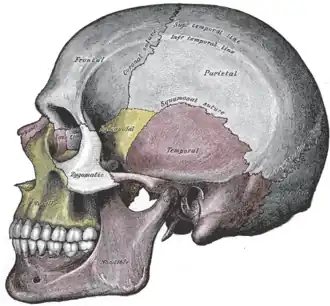

Vista lateral do crânio.

Vista lateral do crânio. -